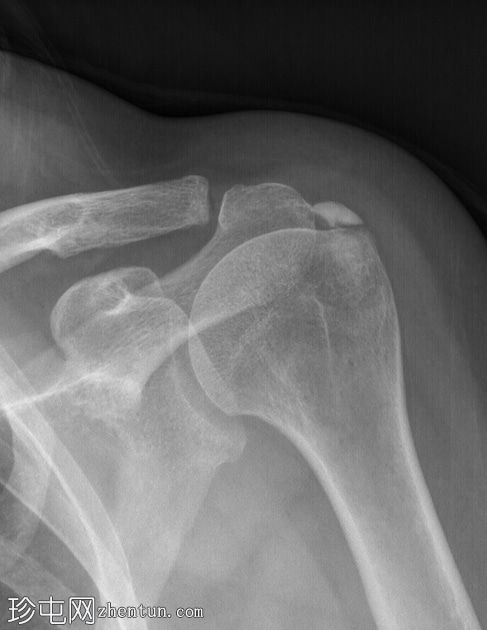

X线片

肩袖钙化,位于冈上肌腱肱骨止点处。

典型的钙化性肌腱炎超声和X线表现。肩袖是最常受累的部位,冈上肌腱受累的病例占80%,本例亦是如此。